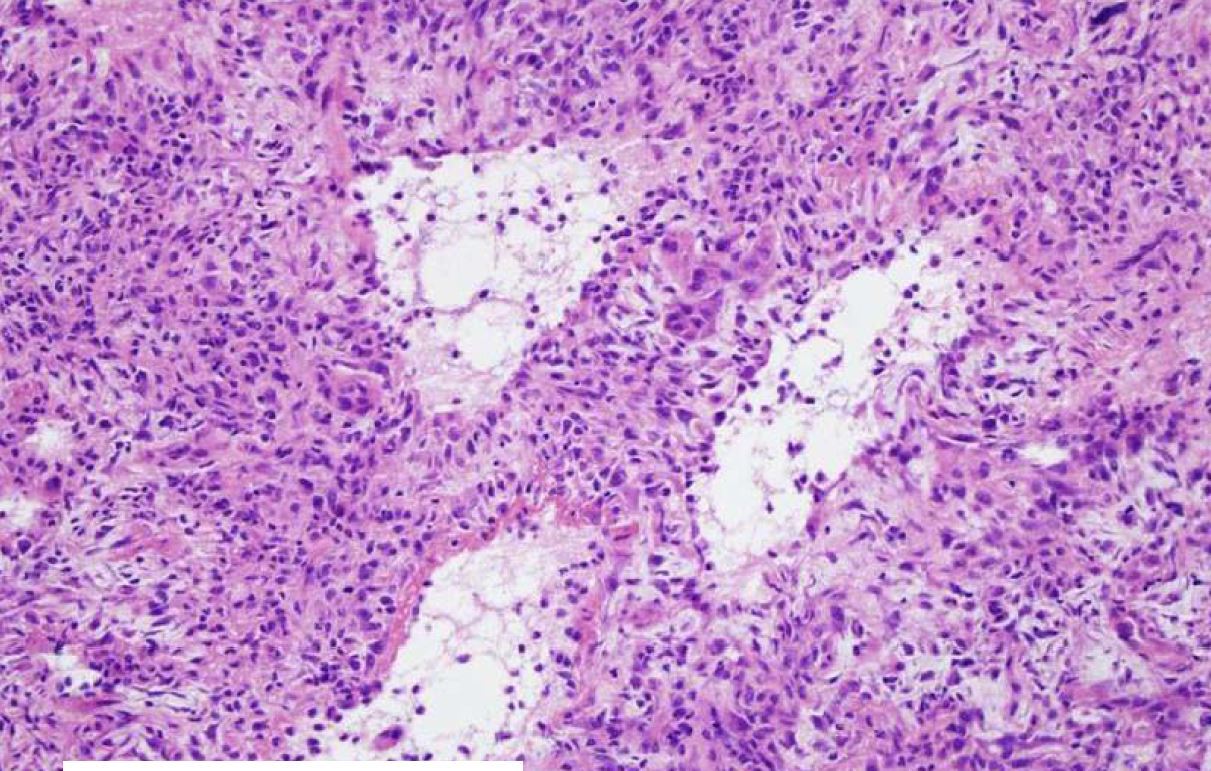

If you see a lung tumor with this appearance, what is diagnose?

A

Pulmonary blastoma (fetal adenocarcinoma)

Primitive glands and stroma, resembles fetal lung